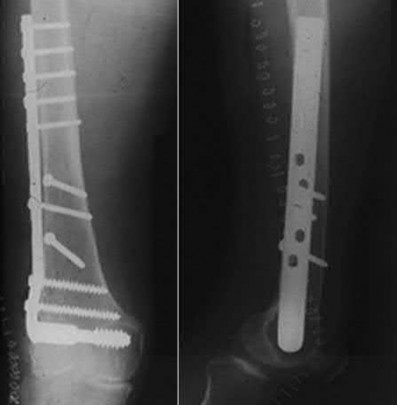

Figures below depict the radiographs obtained from a 60-year-old man with instability and pain 1 year after

primary right total knee arthroplasty. He states that he had surgery on two occasions for a tendon rupture that was repaired with sutures but that his knee popped again, and now the leg is unable to hold his weight. On examination, he is in no acute distress. His height is 6'3", and he weighs 240 pounds. He is ambulatory with crutches. Range of motion of the right knee is 50° to 120° actively and 0° to 120° passively. More than 10° of varus/valgus laxity and more than 5 mm of anteroposterior drawer are present. A palpable defect is observed in the tissue just proximal to the patella. The incision is well healed. The erythrocyte sedimentation rate is 46 mm/h (reference range 0 to 20 mm/h) and the C-reactive protein level is 2.04 mg/L (reference range 0.08 to

3.1 mg/L). Aspiration of the right knee reveals hazy yellow fluid with a white blood cell count of 120 and 1%

neutrophils. No growth of organisms is seen on routine culture. What is the best next step?